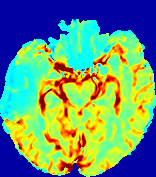

4.3.1 Advection Imaging via Advection-Diffusion

Slice #1Slice #2Slice #3Slice #4Slice #5Slice #6𝐕gt𝟐subscriptnormsuperscript𝐕gt2\|\bf{V}^{\text{gt}}\|_{2}Refer to captionRefer to captionRefer to captionRefer to captionRefer to captionRefer to caption𝐕est𝟐subscriptnormsuperscript𝐕est2\|\bf{V}^{\text{est}}\|_{2}Refer to captionRefer to captionRefer to captionRefer to captionRefer to captionRefer to captionRefer to caption1.51.51.51.21.21.20.90.90.90.60.60.60.30.30.30.00.00.0(mm/s)𝑚𝑚𝑠(mm/s)Destsuperscript𝐷estD^{\text{est}}Refer to captionRefer to captionRefer to captionRefer to captionRefer to captionRefer to captionRefer to caption0.0150.0150.0150.0120.0120.0120.0090.0090.0090.0060.0060.0060.0030.0030.0030.0000.0000.000(mm2/s)𝑚superscript𝑚2𝑠(mm^{2}/s)

Figure 14: PIANO identifiability testing: advection imaging via advection-diffusion. Top row shows 𝐕gt2subscriptnormsuperscript𝐕gt2\|{\bf{V}}^{\text{gt}}\|_{2} used for simulating ground truth pure advection. Rows below show the estimated 𝐕est2subscriptnormsuperscript𝐕est2\|{\bf{V}}^{\text{est}}\|_{2} and Destsuperscript𝐷estD^{\text{est}} on corresponding slices. Note that the plotted value scale for Destsuperscript𝐷estD^{\text{est}} is 0.01 of that for 𝐕gt2subscriptnormsuperscript𝐕gt2\|{\bf{V}}^{\text{gt}}\|_{2} and 𝐕est2subscriptnormsuperscript𝐕est2\|{\bf{V}}^{\text{est}}\|_{2}.

We use the same ‘Advection Imaging’ simulation of Sec. 4.2.1 as the concentration dataset for PIANO. However, instead of modeling pure advection (Eq. 15), we let PIANO estimate both velocity 𝐕estsuperscript𝐕est{\bf{V}}^{\text{est}} and diffusivity Destsuperscript𝐷estD^{\text{est}} via the advection-diffusion PDE (Eq. 2) underlying the proposed PIANO model. Fig. 14 shows the estimated 𝐕est2,subscriptnormsuperscript𝐕est2\|{\bf{V}}^{\text{est}}\|_{2}, and Destsuperscript𝐷estD^{\text{est}} fields for one patient. Although PIANO has the freedom to estimate both a velocity and a diffusivity field from pure advection, PIANO differentiates well between advection and diffusion: the estimated 𝐕est2subscriptnormsuperscript𝐕est2\|{\bf{V}}^{\text{est}}\|_{2} successfully reproduces the ground truth 𝐕gt2subscriptnormsuperscript𝐕gt2\|{\bf{V}}^{\text{gt}}\|_{2} governing the simulated advection process, just as it already did in the ‘Advection Imaging via Advection’ test (Fig. 12). More importantly, the estimated diffusivity Destsuperscript𝐷estD^{\text{est}} is orders of magnitudes smaller than 𝐕est2subscriptnormsuperscript𝐕est2\|{\bf{V}}^{\text{est}}\|_{2}, indicating the estimated diffusion is negligible compared to the estimated advection, which is highly consistent with the underlying pure advection of the simulated data.